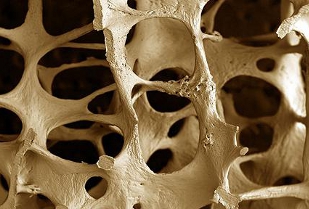

4 settembre 2012

Osteoporosi: come valutare il rischio di fratture da fragilità

Evidence 2012;4(5): e1000015

Osteoporosi: come valutare il rischio di fratture da fragilità

Evidence 2012;4(5): e1000015